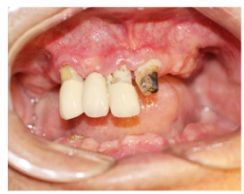

种牙前照片